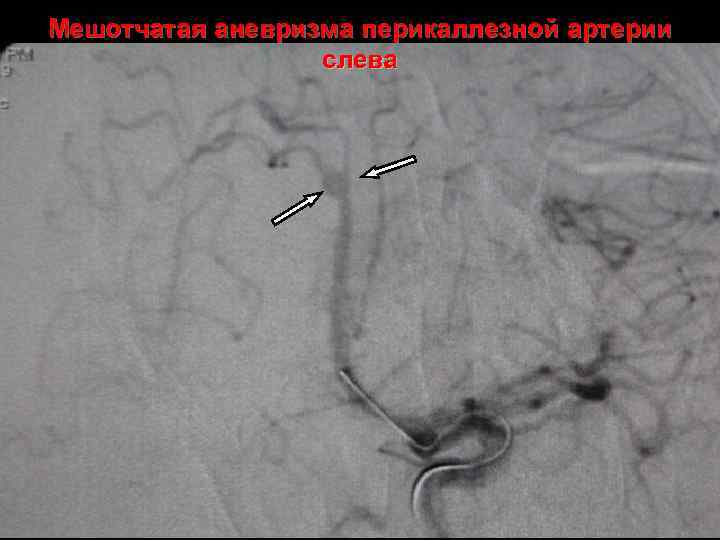

Мешотчатая аневризма перикаллезной артерии слева

После эмболизации аневризмы перикаллезной артерии слева